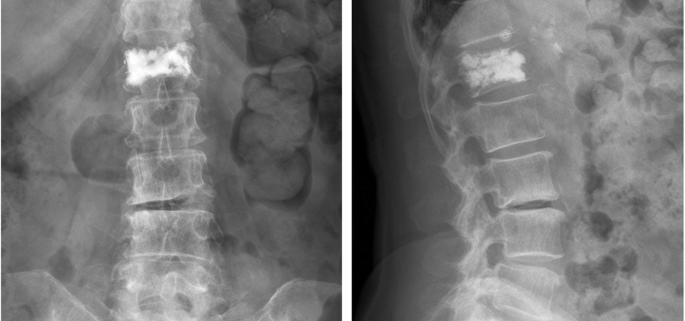

Vertebroplasty is a minimally invasive surgical procedure designed to alleviate the intense pain in patients suffering from a vertebral compression fracture. This type of fracture often comes as a result of osteoporosis, tumor, or any type of traumatic injury. In this procedure, bone cement is injected into the fractured vertebra, stabilizing the fracture and significantly reducing pain.

Although there isn’t a specific classification for vertebroplasty, it usually goes hand in hand with another procedure called kyphoplasty. While vertebroplasty involves injecting bone cement into a vertebral fracture, kyphoplasty includes an extra step. In kyphoplasty, a small balloon is first inserted and inflated to create a cavity, and then the bone cement is injected. Both procedures aim to deal with different aspects of vertebral fractures.

- Imaging tests: These include X-rays to reveal the fractures, CT scans for detailed images, and MRI to evaluate damage to soft tissues and detect tumors.

- Vertebroplasty: This minimally invasive procedure stabilizes the fracture and provides significant pain relief.